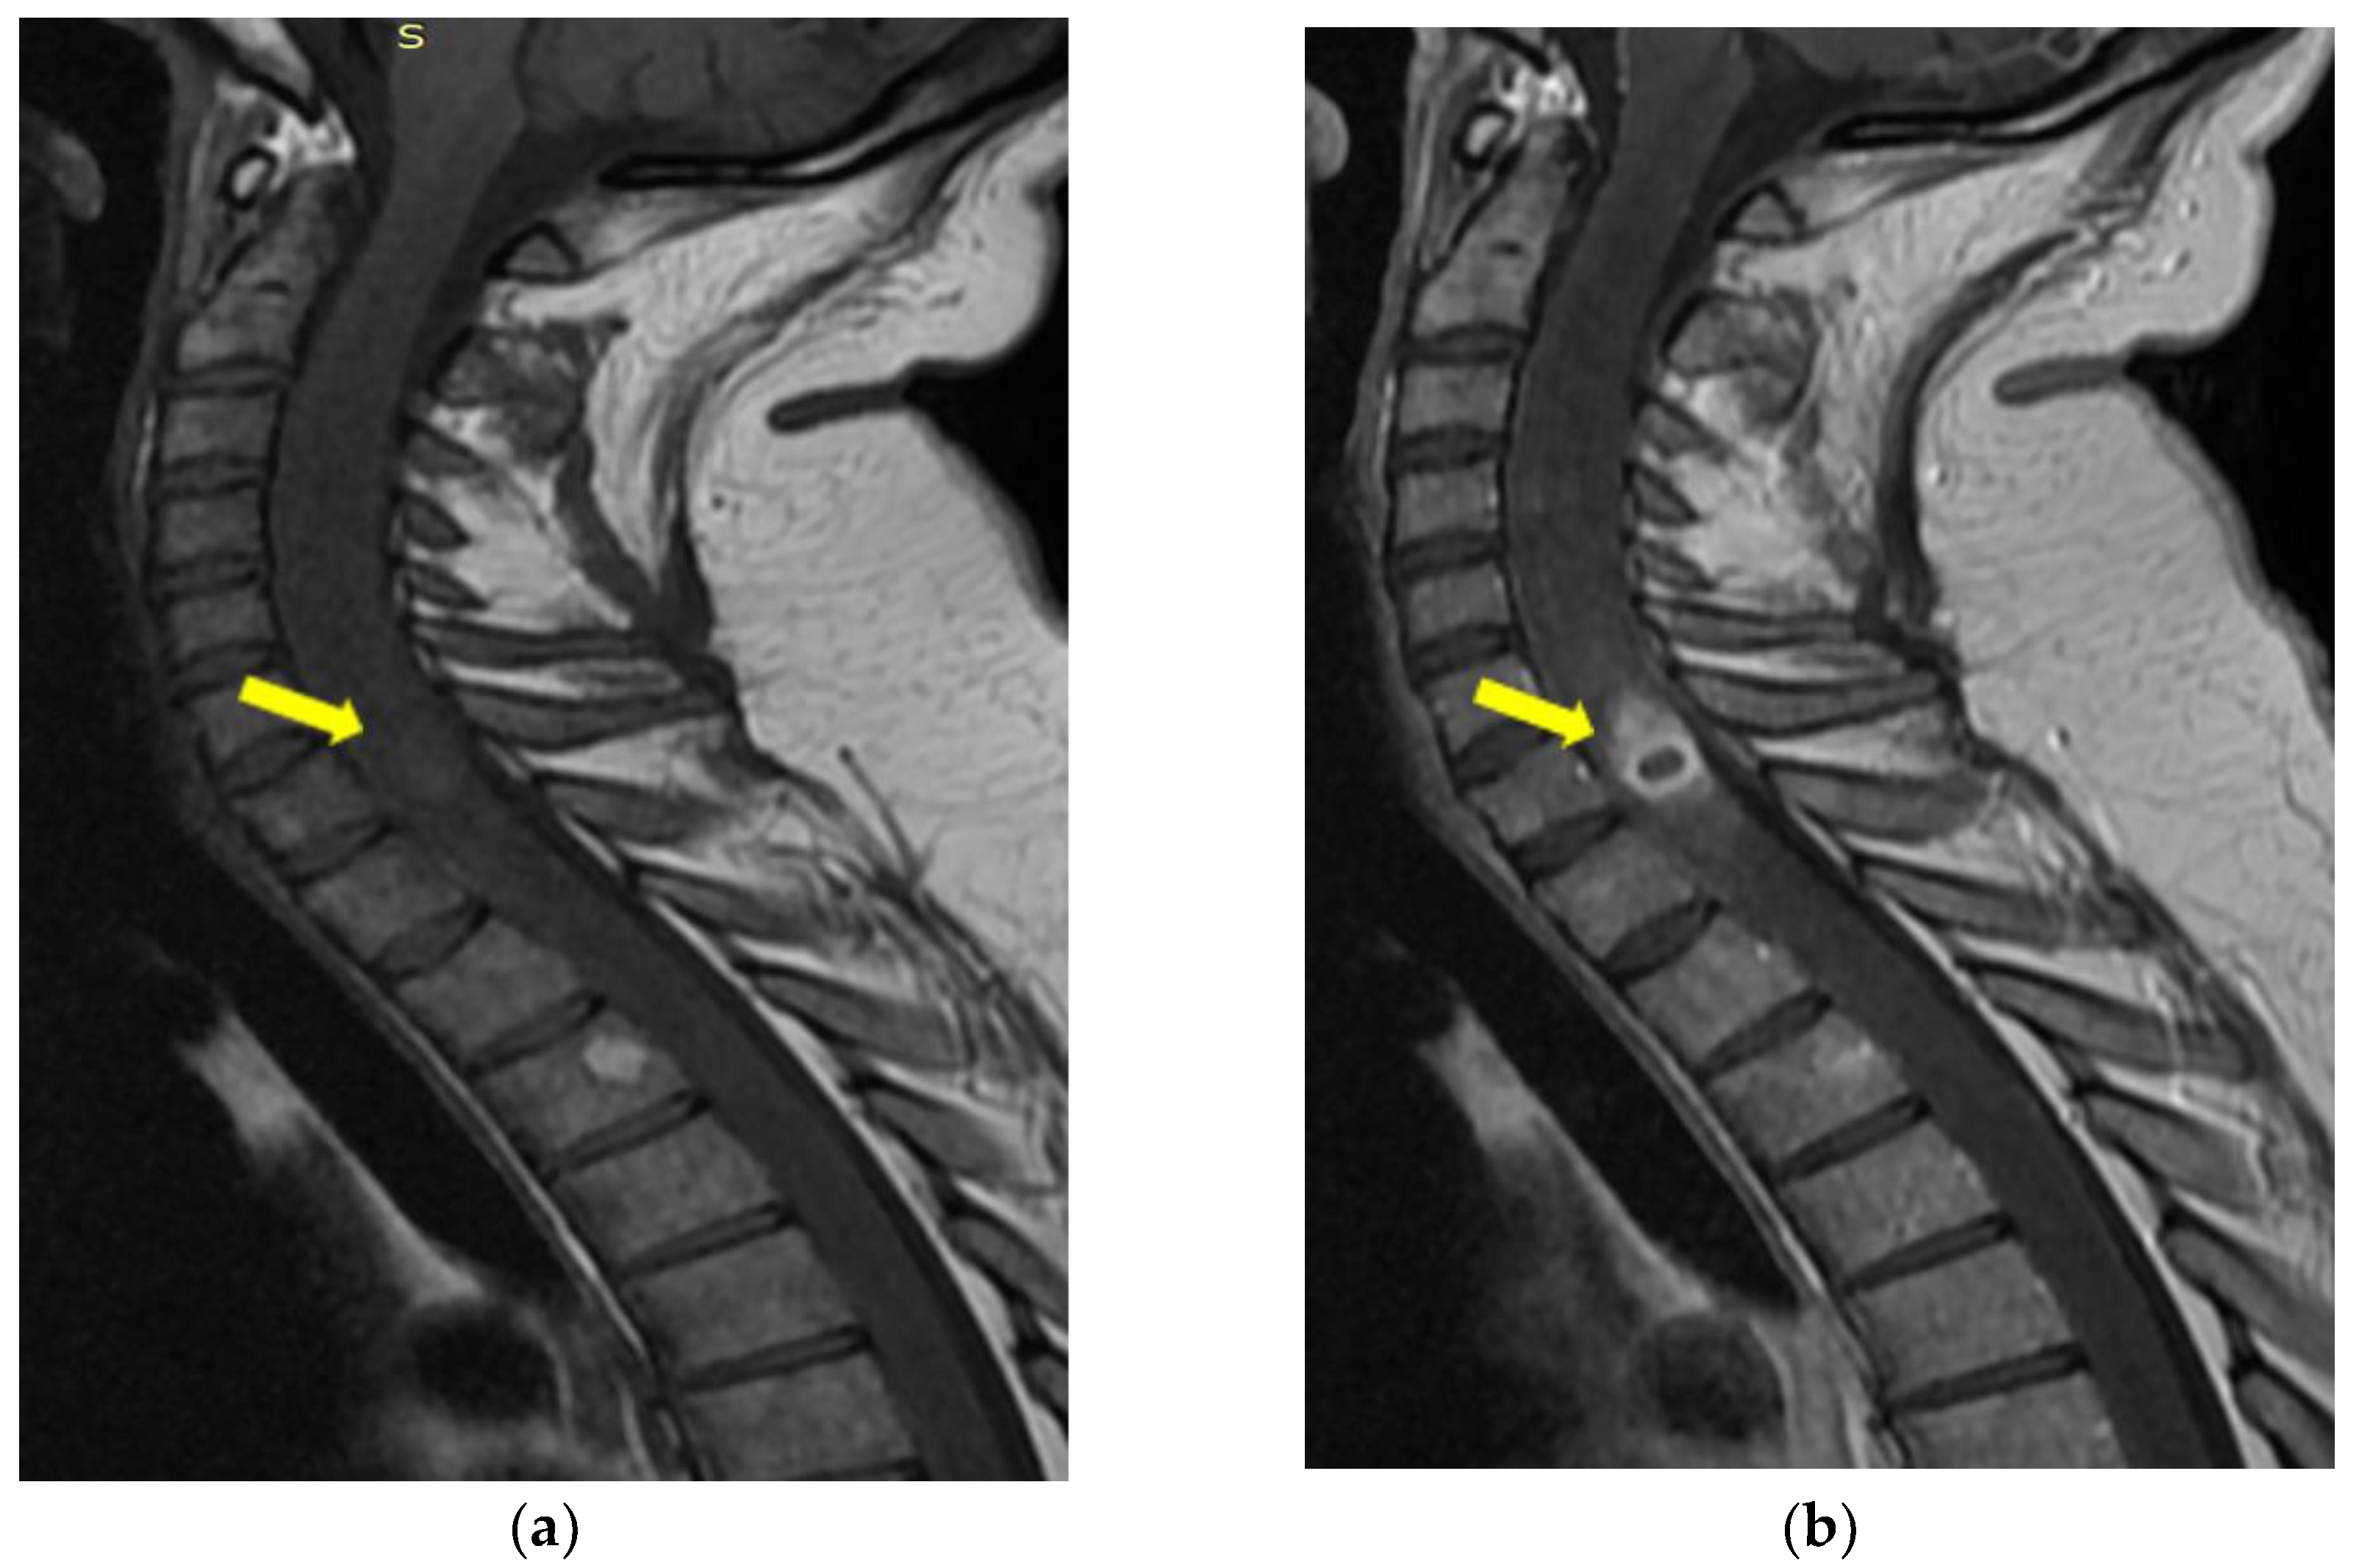

Cervico-Dorsal Intramedullary Spinal Cord Abscess with Aspergillus fumigates following Pulmonary Infection in an Immunocompetent Patient

Mereuta, V.D.; Sava, A.; Stan, C.I.; Eva, L.; Dumitrescu, G.F.; Dobrin, N.; Tudorache, C.; Chiriac, A.; Strambu, I.R.; Chiran, D.A.; et al. Cervico-Dorsal Intramedullary Spinal Cord Abscess with Aspergillus fumigates following Pulmonary Infection in an Immunocompetent Patient. Medicina 2023, 59, 806. https://doi.org/10.3390/medicina59040806